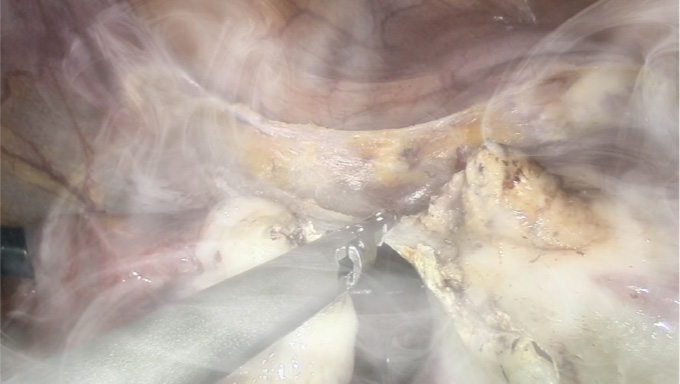

Using image signal processing technology, smoke signals in images can be removed, allowing for clear observation even in the presence of smoke